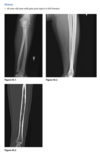

Radiographs of the right tibia and fib-

ula (Figs. 2.21.1 and 2.21.2) show a vague, irregu-

lar linear radiolucency within an area of sclerosis

in the distal third of the tibia (arrowheads). Coronal

T1-weighted MRI of the tibia reveals a serpiginous

region of decreased marrow signal extending over

several centimeters (Fig. 2.21.3, arrows) and a de-

fect in the lateral tibial cortex (curved arrow). Axial

T2-weighted MRI through the same region demon-

strates a bony sequestrum (Fig. 2.21.4, arrowhead)

and increased signal intensity (i.e., marrow edema)

within the tibia. A sinus tract extends through the

lateral aspect of the posterior tibia (white arrow) to

the skin surface anteriorly (black arrow), with edem-

atous changes in the subcutaneous tissues.

Chronic osteomyelitis with a draining

sinus tract

In acute

osteomyelitis, the earliest radiographic sign is ob-

scuration of the normal fat planes as a result of soft-

tissue swelling. Bony changes usually do not appear

until 1 to 2 weeks after the onset of the infection.

Osteomyelitis typically affects the epiphysis in in-

fants and adults and the metaphysis in children and

is multifocal in neonates. The MRI features of acute

osteomyelitis include areas of diminished signal in-

tensity on short TE images within the normally high.

signal intensity of the fatty bone marrow. Long TE

images with fat-suppression or inversion-recovery

images usually show areas of increased signal inten-

sity in muscle, cortical bone, and periosteum that

are not well demonstrated on short TE sequences.

T1-weighted fat-suppressed, gadolinium-enhanced

images increase sensitivity and specificity in the di-

agnosis of infection.

The radio-

graphic findings of chronic osteomyelitis include

prominent cortical thickening and a mixed pattern

of osteosclerosis and osteolysis. Signs suggesting re-

activation of infection include the development of

new, ill-defined areas of osteolysis; thin, linear peri-

ostitis; or the presence of a sequestrum and draining

sinus tract.

An unusual complication of a long-standing

draining sinus tract in chronic osteomyelitis is squa-

mous cell carcinoma.